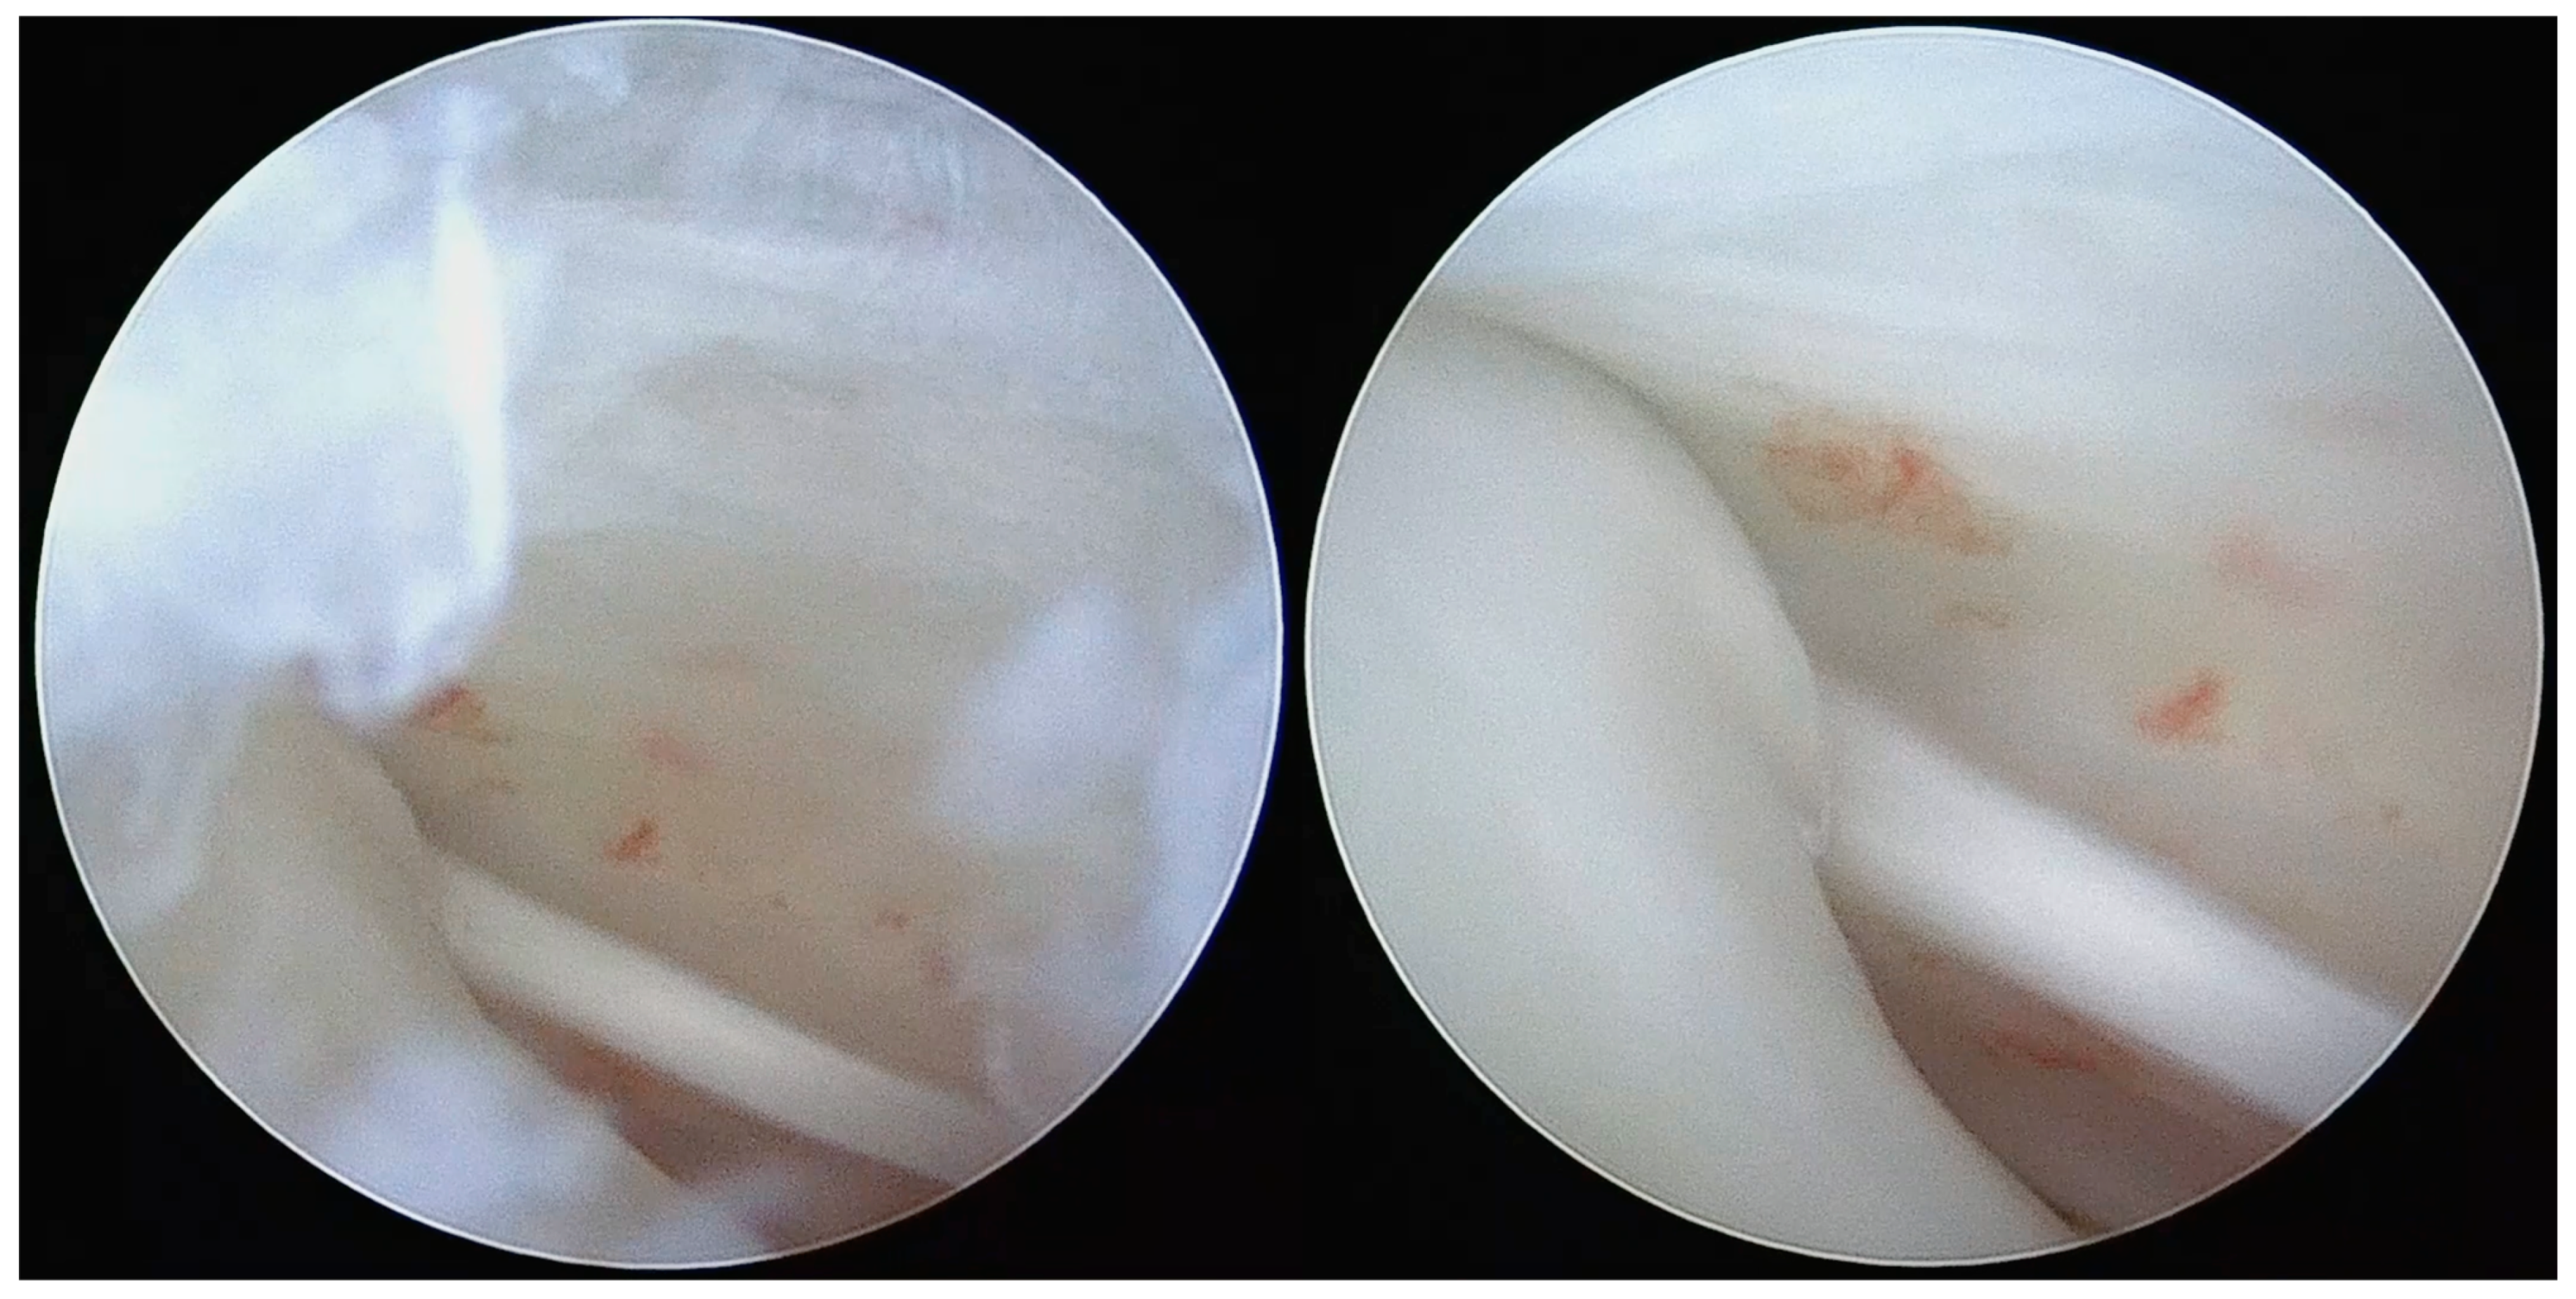

Figure 1.

Arthroscopic view of adhesions and moderate to severe synovitis.

Figure 2.

Disk perforation with condyle head exposure and exploration of inferior articular compartment.